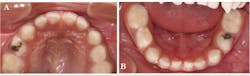

We applied SDF (Advantage Arrest, Elevate Oral Care LLC) and resin-modified glass ionomer (Fuji II LC, GC America Inc.) temporary restorations to the carious lesions on teeth Nos. B and L, and continued to monitor them at three-month intervals. After one year of follow-up, the restorations were intact, and the family had made dramatic improvements in controlling the primary etiologic factor (figure 3). After two years of follow-up, the temporary restoration on tooth No. L fell out and required replacement (figure 4).

Figure 3: SDF plus resin-modified glass ionomer was placed on teeth Nos. B and L using the SMART technique. Restorations were intact 12 months later (tooth No. B shown in photo A, and tooth No. L shown in photo B).